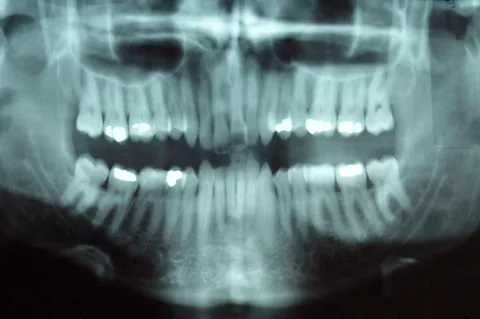

Other recent approaches have focused on finding ways to get our teeth to heal themselves. Ruchi Sahota, a dentist in California and a spokesperson for the American Dental Association, suggests visualising the anatomy of a tooth like an apple. “They have a thin enamel shell, like the skin of an apple, that protects the inner core, which is the dentin of the tooth. And just like the seeds of an apple, we have the nerve of our tooth,” she said. “A cavity tends to form in the enamel. When it gets into the dentin, you need to fill it at the dentist. When it gets to the nerve, that’s when you need a root canal.”

AlamyOther approaches use the cells that are in our teeth to heal cavities that have already penetrated the enamel, by stimulating the creation of dentin, the calcified tissue that makes up the inner portion of our teeth. Recent research published in the journal Science Translational Medicine for example, found that treating exposed tooth pulp in rats with low-power laser light before filling the cavity could induce stem cells to create dentin in the tooth.